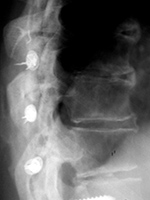

Harrington rods |

The hooks on these rods are designed for distraction. From Hunter, 2004 |

Harrington rods are at the thoracolumbar junction stabilizing a vertebral body fracture. The hooks (thick arrows) anchor the rods in the lamina. Segmental wires around the lamina (thin arrow) supplement the fixation. From Benjamin, 1994 |